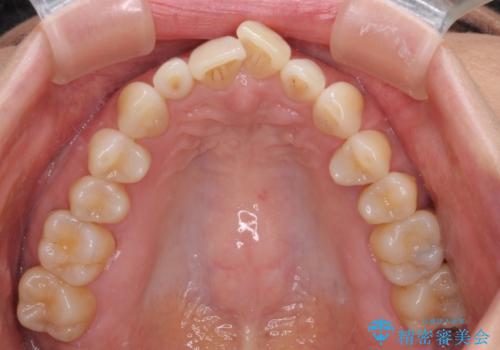

前歯のスペースが気になる インビザラインによる矯正治療

- 前歯の上下スペースによる食べにくさを気にして来院された患者様です。

インビザラインにより上下の前歯の隙間を閉じていくこととしました。

舌の突出癖があると上下前歯にスペースが開くため、矯正治療を機会に舌癖を改善するトレーニングを行ってもらい、矯正治療後の後戻りを防止するように指導しています。